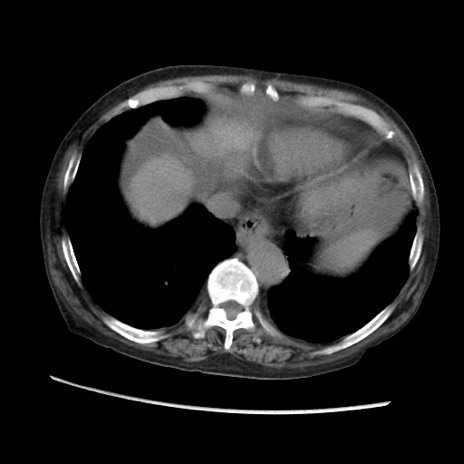

症例31(横断像)

【症例】80歳代 女性

【主訴】腹部膨満感

【現病歴】他院にて肝硬変にてフォロー中。1週間前から便秘、腹部膨満感、臍部腫瘤あり受診となる。

【既往歴】肝硬変

【身体所見】腹部膨隆あり、皮膚変化なし、疼痛なし。

【データ】WBC 4600、CRP 0.25